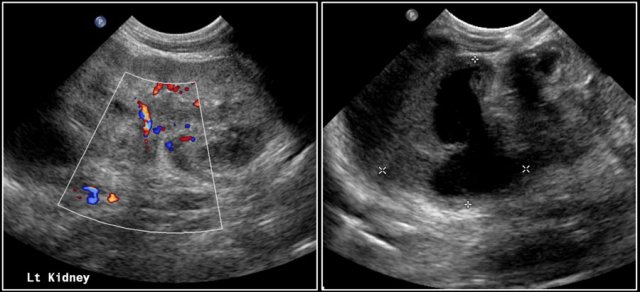

One-year-old boy was referred with a diagnosis of a cystic nephroblastoma.

Ultrasound detected a huge cyst in the middle of the abdomen.

When examined from the left flank with a high frequency linear array probe some parenchymal tissue was visible surrounding very dilated calyces. This is compatible with an extreme hydronephrosis.

At first it was thought that there were some solid parts in the cyst.

But when pressure was applied with the probe this proved to be debris.

MRI depicts the hydronephrosis with more overview.

The cause was a pyeloureteric stenosis.

The left kidney had 33% split renal function on renography.

A pyelum reconstruction was successfully performed.